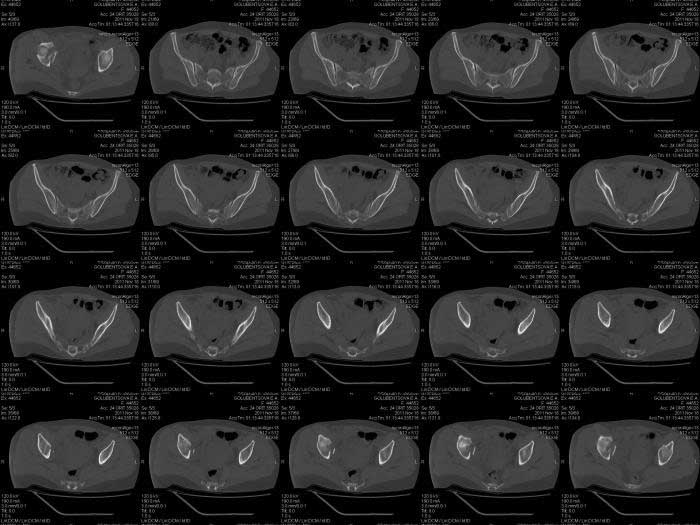

Кт снимки

КТ срезы помогают увидеть мелкие фрагменты и маргинальную импакцию, но на ваших мелких срезах трудно увидеть повреждение боковой массы крестца? Классифицировать перелом вертлужной впадины по Летурнелю все таки привычнее на косых Judet снимках.

Некоторые переломы вертлужной впадины между собой трудно отличаются, и надо проводить дифференциальную диагностику переломов: Т-образного, двух колонного и комбинации поперечного с переломом задней стенки (Associate

Transverse &Posterior Wall). Отсутствие вовлечения крыла подвздошной кости при двухколонном и наличие перелома в седалищной кости говорит о

Т-образном переломе.